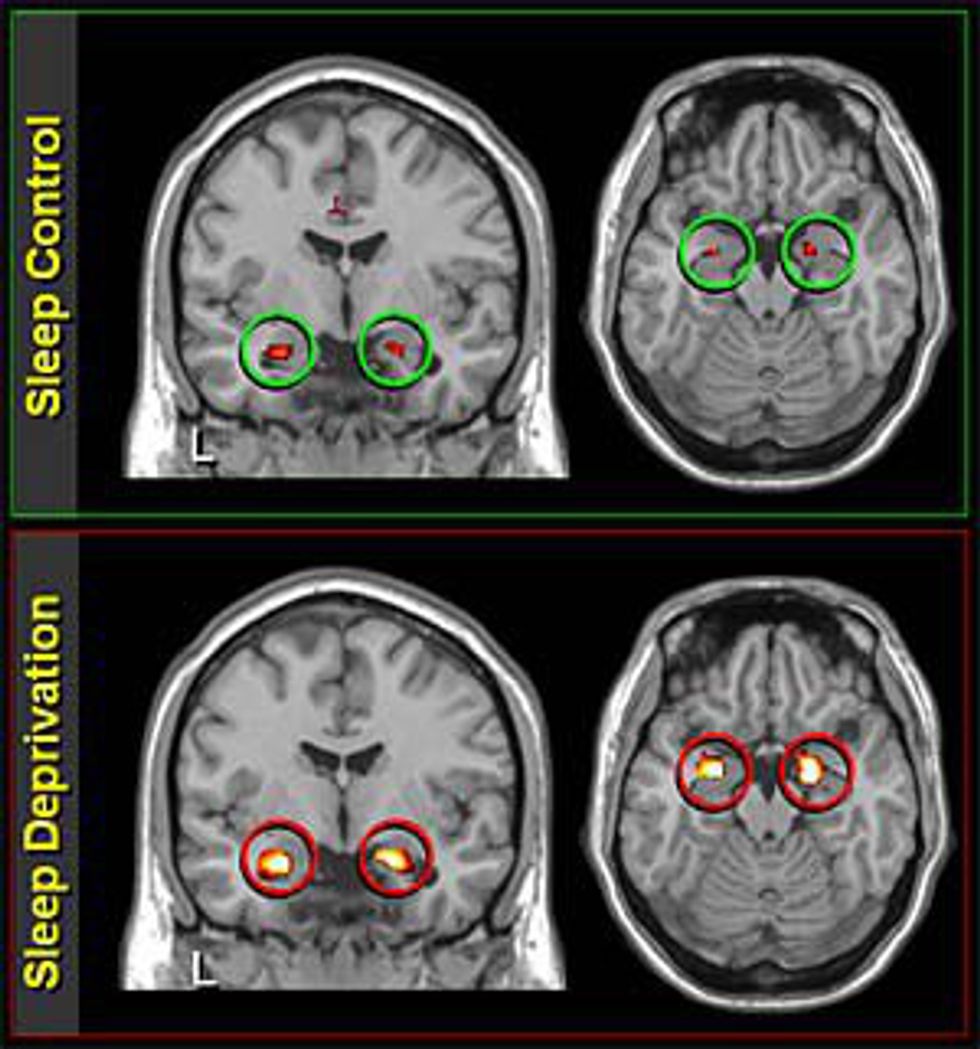

The image below is an X-ray of a brain with adequate amounts of sleep, and one suffering from sleep deprivation.

"Results from a brain imaging study suggest that while a good night's rest can regulate your mood and help you cope with the next day's emotional challenges, sleep deprivation does the opposite by excessively boosting the part of the brain most closely connected to depression, anxiety and other psychiatric disorders.

"It's almost as though, without sleep, the brain had reverted back to more primitive patterns of activity, in that it was unable to put emotional experiences into context and produce controlled, appropriate responses," said Matthew Walker, director of UC Berkeley's Sleep and Neuroimaging Laboratory and senior author of the study,

That's because the amygdala, the region of the brain that alerts the body to protect itself in times of danger, goes into overdrive on no sleep, according to the study. This consequently shuts down the prefrontal cortex, which commands logical reasoning, and thus prevents the release of chemicals needed to calm down the fight-or-flight reflex." - Yasmin Anwar, UC Berkeley News

Basically, sleep becomes the least of your worries when you try to operate without it.